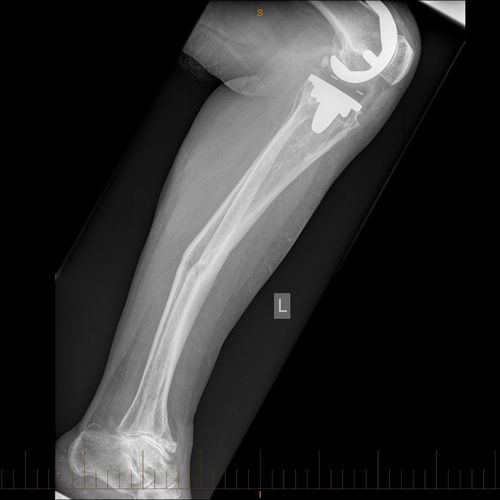

Adult with Circular Frame Correction of the Post-Traumatic Deformity of the Tibia